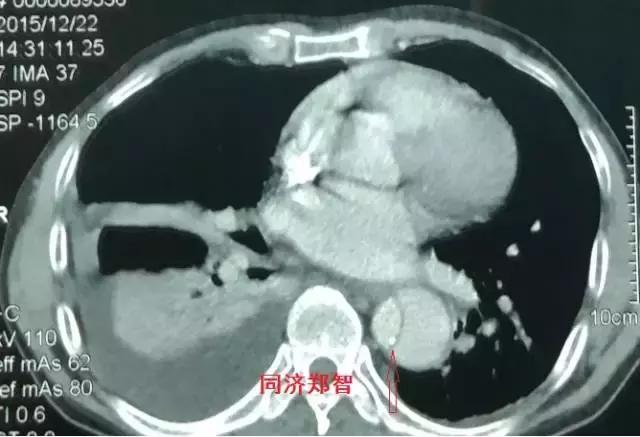

第三招 神奇的钙化点征

正常主动脉的血管可能有钙化,在没有病变的主动脉壁,钙化点一般在主动脉外周一圈,当血管内出现内移的钙化点,则提示内膜片内移,可能是病变的征象。

病例九

平扫CT提示降主动脉内膜片征,同时内膜片中可见一钙化点。CTA证实为B型主动脉夹层。